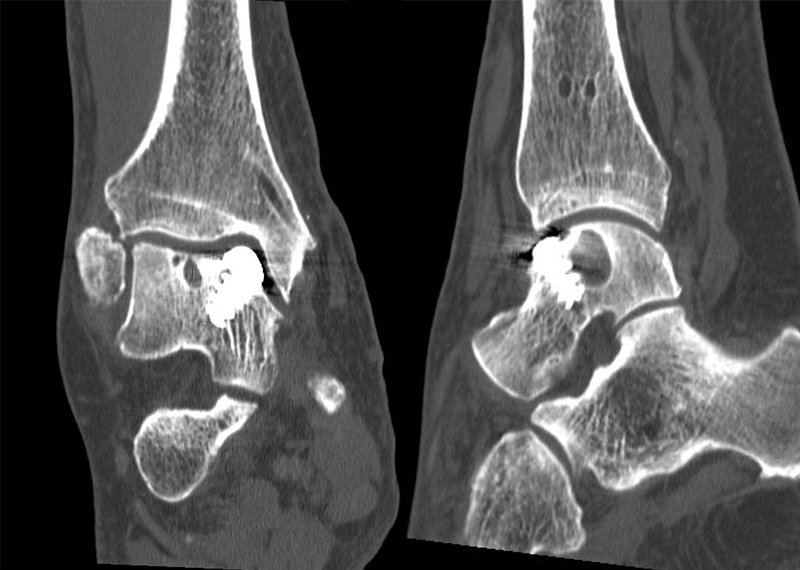

Der Computertomographie (CT) fehlt ebenfalls die Fähigkeit, den Knorpel direkt zu bewerten. Mit dem CT können jedoch weitere Details der knöchernen Verletzung, wie Größe, Form, Umfang und evtl. Dislokation der Läsion beurteilt werden 11. Insbesondere kleine Knochenkanten oder Gelenkkörper lassen sich in der CT wesentlich besser darstellen als mit einem MRT.

Zur Vollansicht und zum Lesen der Bildbeschreibung bitte das Bild anklicken.